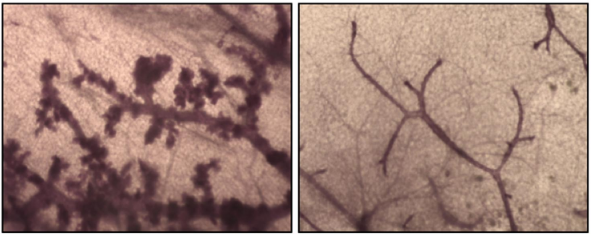

Penninger博士的研究结果表明,RANK的失活显著延迟,并且在一些情况下甚至阻止了具有突变的BRCA1的小鼠中乳腺癌的发展。RANK的丧失也削弱了乳腺肿瘤向高度恶性肿瘤的发展。当RANK基因失活和当小鼠接受预防性药理性RANKL抑制剂时,可以观察到这些效应。

Penninger博士记录RANK / RANKL在患有BRCA突变的女性的恶性前病变和乳腺癌中高度表达,并且RANK的常见变体与这些女性中增加的乳腺癌风险相关。未来的实验,特别是仔细设计的临床试验,将需要评估RANKL抑制剂是否提供优于目前的预防技术,如他莫昔芬或卵巢切除术的优势。然而,这些发现提高了令人兴奋的可能性,RANKL抑制剂已经是具有良好安全记录的药物并且被食品和药物管理局批准,可以提供用于妇女的乳腺癌预防。